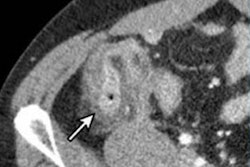

The team compared the diagnostic performance for detecting diverticulitis on CT between radiologists using a headset (Apple Vision Pro) and a desktop viewer app (Visage Ease VP) via a study that included 110 patients who underwent abdomen/pelvis CT scans (and for which the exam report noted the presence or absence of diverticulitis). Six radiologist readers rated the exams on a six-level scale for the condition (1 = no diverticulitis, 6 = diverticulitis). The readers also completed a five-level survey on ease of use of the headset and the desktop computer viewer app (1 = difficult, 5 = easy); about their experience with the headset (1 = bad, 5 = good); and about their preference between devices (1 = desktop, 5 = headset). The investigators also tracked interpretation time per case.